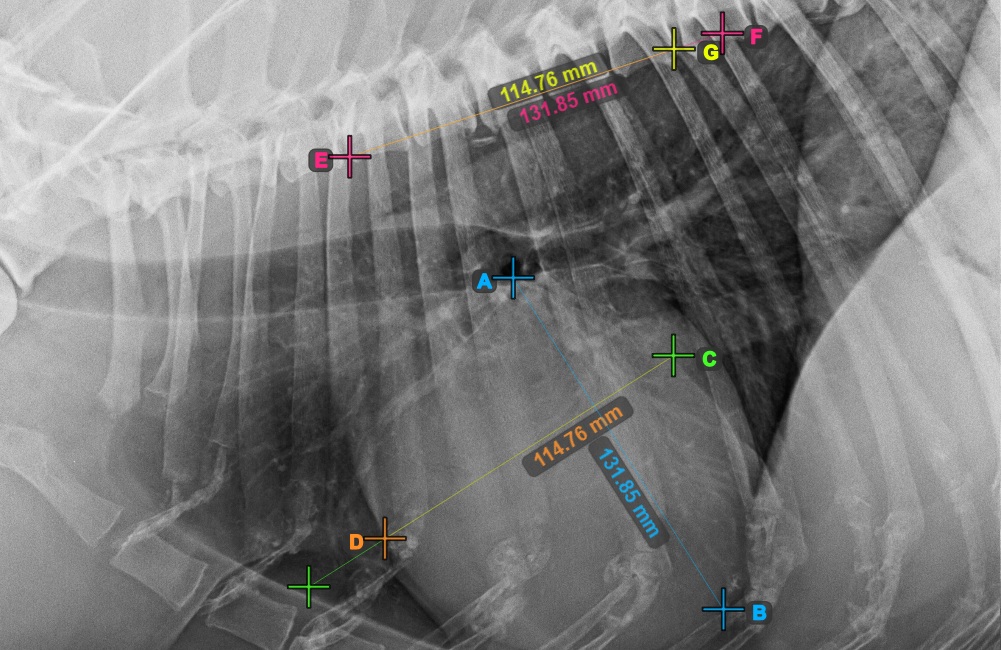

Indítsa el a mérést a Bifurcatio tracheae megjelölésével, a szív felső részéhez közel.

Az alábbi kép a Bifurcatio tracheae pont tipikus elhelyezkedését mutatja.

Fejezze be a szív hosszanti tengelyét az Apex pont megjelölésével, a szív alsó részéhez közel.

Az alábbi kép az Apex pont tipikus elhelyezkedését mutatja.

Folytassa a mérést a szív rövid tengelyének legszélesebb jobb (feji) pontjának megjelölésével.

Az alábbi kép a szív rövid tengelyének „legcranialisabb” pontjának tipikus elhelyezkedését szemlélteti

Fejezze be a szív rövid tengelyét a legszélesebb bal (caudal) pont megjelölésével.

Az alábbi kép a szív rövid tengelyének „legcaudalisabb” tipikus elhelyezkedését mutatja.

Azonosítsa a T4 csigolya kezdetét (a gerinc negyedik csigolyatestét), a gerinc kezdőpontjától számítva. Jelölje meg a T4 csigolya kezdetét a mérés folytatásához. A szoftver a megjelölt pontból vonalakat húz a gerinc mentén. A vonalak hossza a szív mért hossz- és rövidtengelyétől függ.

Az alábbi kép a gerinc negyedik csigolyatestének kezdetén lévő pont tipikus elhelyezkedését mutatja.

A szükséges VHS-kalkulációk elvégzése előtt győződjön meg róla, hogy a vonalak pontosan a csigolyák mentén helyezkednek el.